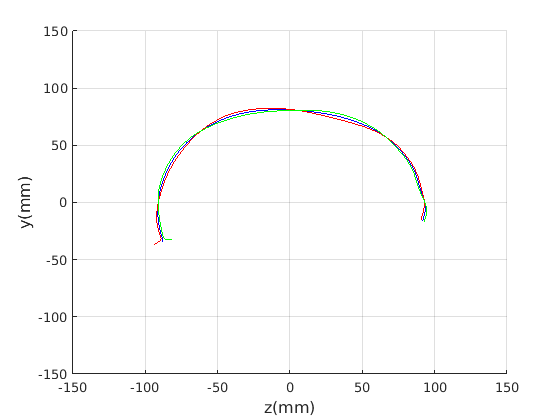

Figure 16 shows examples of the robust ellipse fit for four head profiles. The centre of the ellipse is used in a pose normalisation procedure where the ellipse centre is used as the origin of the profile and the angle from the ellipse centre to the nasion is fixed at -10 degrees. We call this Ellipse Centre - Nasion (ECN) pose normalisation and later compare this to GPA. The major and minor axes of the extracted ellipses are plotted as red and green lines respectively in Fig. 16.

|

Figure 17 shows all 100 profiles overlaid with the same alignment scheme. The median value of major ellipse axis and the ellipse centre-nasion angle differ by 3.6 degrees, so that when the nasion angle is fixed at -10 degrees, the median ellipse angle is -6.4 degrees (cf. -7.4 degrees with manual landmarking of the nasion). We noted regularity in the orientation of the fitted ellipse as is indicated by the clustering of the major (red) and minor (green) axes in Fig. 17 and the histogram of ellipse orientations in Fig. 18. For most people, the major axis of the ellipse is closely aligned with the y-axis (upright), and titled slightly forwards. A minority of heads (9%) in the training sample have their major ellipse axes closer to the vertical (these relatively tall and short heads are known as brachycephalic.) Ellipse axis clustering (relative to the fixed ellipse centre-nasion line) does not appear to be sharply defined. This is because many crania are close to circular in cross-section, making the orientation of these angles sensitive to small changes in shape from one person to the next. Note also the variation at the back of the head due to a variety of hair styles, some of which protrude from under the cap. We limit the region over which we model the cranial shape in order to crop this unwanted data out.